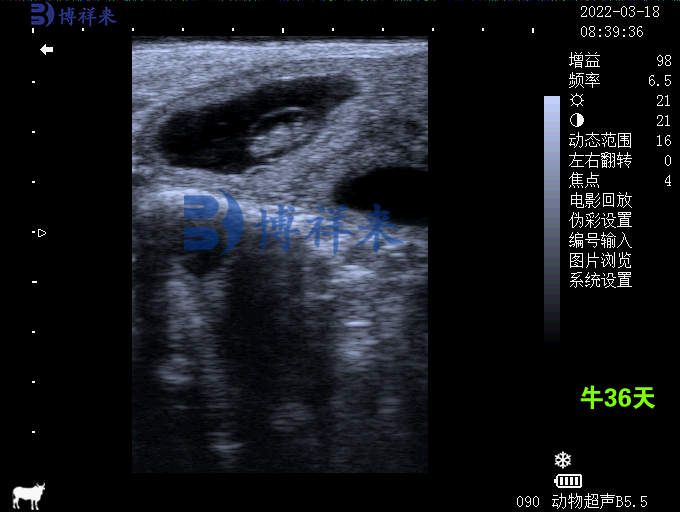

建议: 根据母牛体型、孕期阶段适当调整频率(如3.5MHz/5MHz)和增益值。